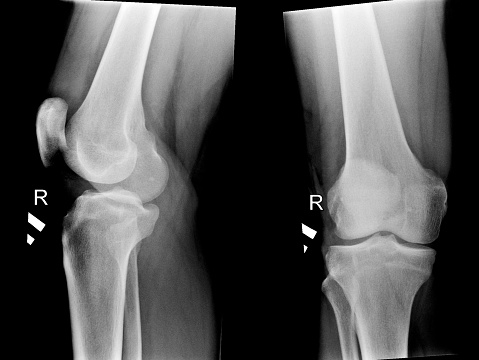

If you’re over the age of 50, then bone health is a serious concern—even more so if you’re a woman. When a person develops osteoporosis, their bones become weak and brittle, which increases the risk of fractures. Osteoporosis also negatively impacts mobility and can lead to isolation and depression. Osteoporosis is often called “the silent ...click here to read more